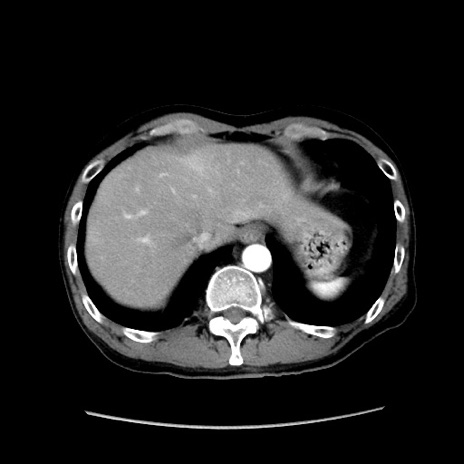

冠状断像

症例37(横断像)

【症例】40歳代 男性

【主訴】腹痛

【現病歴】4時間ほど前に電車に乗車中に臍部上より腹痛出現。徐々に増悪し起立困難となり、救急外来受診。生ものは数日食べていない。今朝お雑煮を食べた。

【身体所見】BT 36.8℃、BP 117/84mmHg、HR 91/min、SpO2 97%、苦悶様、腹部:臍上部広範囲圧痛あり、反跳痛±

【データ】WBC 8100、CRP 0.03